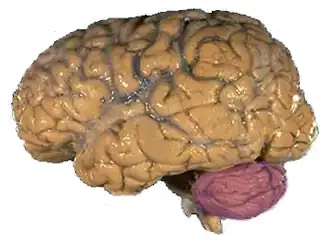

Intention tremor is a dyskinetic disorder characterized by a broad, coarse, and low-frequency (below 5 Hz) tremor evident during deliberate and visually-guided movement (hence the name intention tremor). An intention tremor is usually perpendicular to the direction of movement. When experiencing an intention tremor, one often overshoots or undershoots one's target, a condition known as dysmetria.[1][2] Intention tremor is the result of dysfunction of the cerebellum, particularly on the same side as the tremor in the lateral zone, which controls visually guided movements. Depending on the location of cerebellar damage, these tremors can be either unilateral or bilateral.[1]

More persistent intention tremors are often caused by damage to certain regions of the brain. Their most common cause is damage and/or degeneration in the cerebellum, the part of the brain responsible for motor coordination, posture, and balance, and especially fine motor movements. When the cerebellum is damaged, a person may have difficulty executing a fine motor movement, such as attempting to touch one's nose with one's finger. One common way for the cerebellum to become damaged is through the development of cerebellar lesions.[13] The most common site for cerebellar lesions that lead to intention tremors has been reported to be the superior cerebellar peduncle, through which all fibers carrying information to the midbrain pass, and the dentate nucleus, which is also responsible for linking the cerebellum to the rest of the brain.[3] Alcohol abuse is one typical cause of this damage to the cerebellum. The alcohol abuse causes degeneration of the anterior vermis of the cerebellum. This leads to an inability to process fine motor movements in the individual and the development of intention tremors. In MS, damage occurs due to demyelination and neuron death, which again produce cerebellar lesions and an inability for those neurons to transmit signals.[13] Because of this tight association with damage to the cerebellum, intention tremors are often referred to as cerebellar tremors.[1]

Intention tremors can also be caused as a result of damage to the brainstem or thalamus. Both of these structures are involved in the transmission of information between the cerebellum and the cerebral cortex, and between the cerebellum and the spinal cord, and then on to the motor neurons. When these become damaged, the relay system between the cerebellum and the muscle upon which it is trying to act is compromised, resulting in the development of a tremor.[13]

A working diagnosis is made from a neurological examination and evaluation. Parts of a complete examination include a physical examination, magnetic resonance imaging (MRI), patient history, and electrophysiological and accelerometric studies. A diagnosis of solely intention tremor can only be made if the tremor is of low frequency (below 5 Hz) and without the presence of any resting tremors.[1] Electrophysiological studies can be useful in determining frequency of the tremor, and accelerometric studies quantify tremor amplitude. MRI is used to locate damage to and degradation of the cerebellum that may be causing the intention tremor. Focal lesions such as neoplasms, tumors, hemorrhages, demyelination, or other damage may be causing dysfunction of the cerebellum and correspondingly the intention tremor.[14]